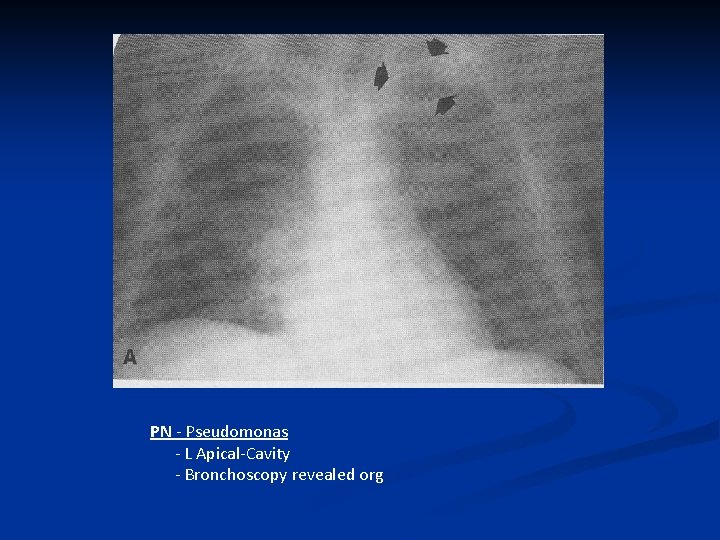

PN - Pseudomonas - L Apical-Cavity - Bronchoscopy revealed org